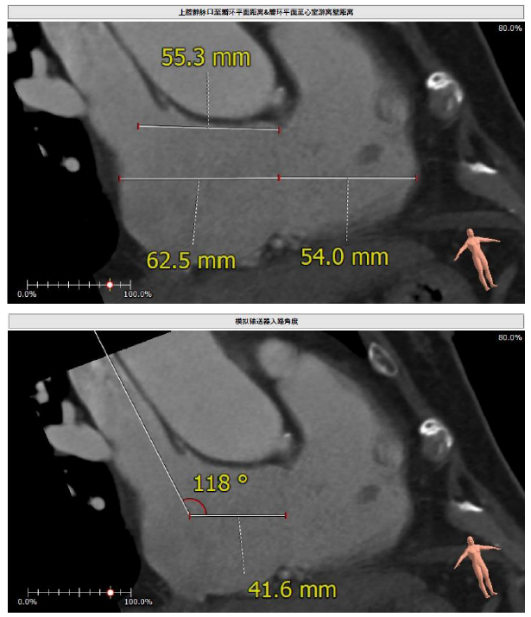

接受本次治疗的是一例三尖瓣重度反流的患者,NYHA心功能Ⅲ级。主诉“反复活动后气促1年,下肢水肿4个月”。入院N末端B型脑钠肽前体(NT-proBNP)3161pg/ml。心电图提示:心房颤动,ST-T改变。术前超声提示:重度三尖瓣关闭不全,右心房扩大,三尖瓣收缩期位移(TAPSE)14mm,左房增大,左室收缩功能正常低值,主动脉瓣、二尖瓣机械瓣功能良好。术前CT评估(图1):三尖瓣瓣环(周长换算直径)大小为46.2mm;入路血管无严重迂曲,无钙化;双侧冠脉有钙化。

图1. 术前CT评估结果